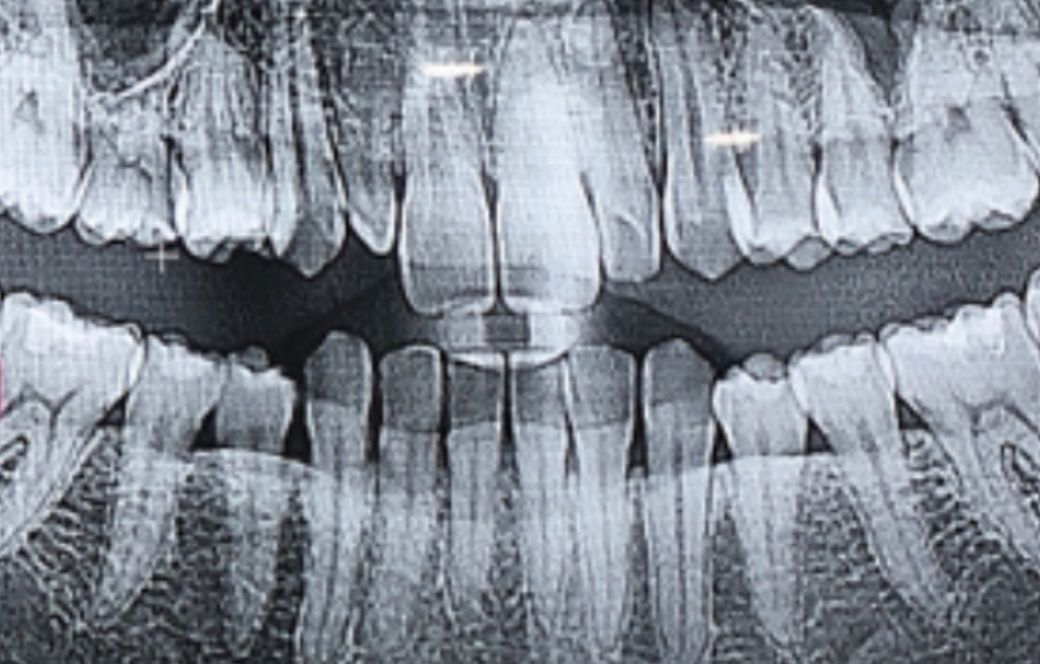

어렸을때 이빨을 뽑았는데 그 이후로 앞니 옆에 이빨 하나가 조금만 자라고 그 이후로 자라질 않아요..ㅠㅠ

• 1번 째 사진

사진으로 봤을때 치아가 굉장히 작습니다

레진이나 라미네이트로는 쉽지 않을듯 하고, 크라운을 씌우는게 가장 좋을것으로 보입니다.